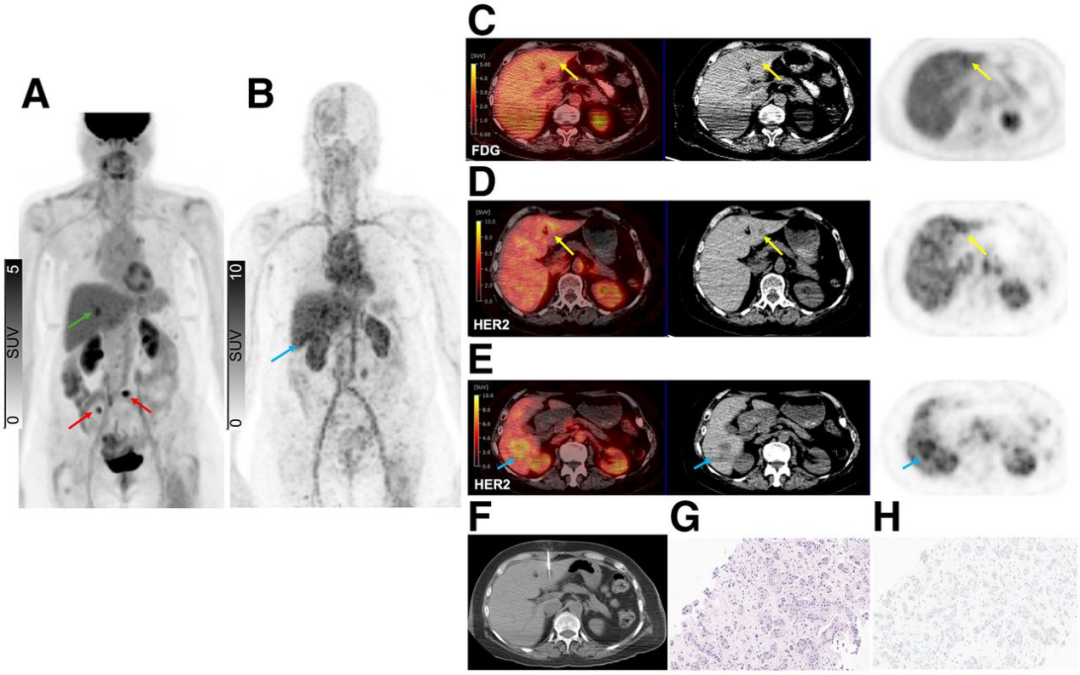

来自89Zr-ss-帕妥珠单抗队列的代表性患者展示了HER2表达的全谱系分布,图2-4展示了不同病例的HER2 PET图像和相应的病理结果。图2显示了一个HER2阳性胸骨病灶,图3显示了同一患者体内的HER2-0和HER2低表达骨病灶,图4显示了一个HER2-0肝脏病灶。

图4. 一例患者HER2 PET显示的HER2-0肝脏病灶